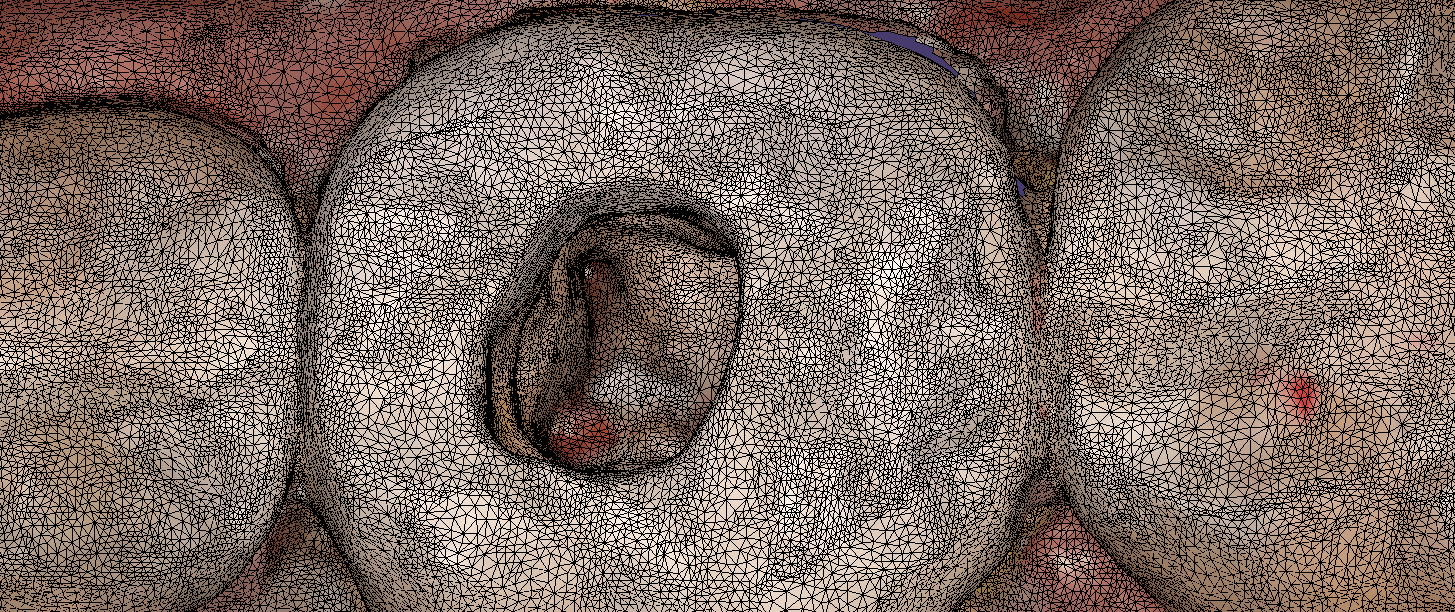

Imaging depth and red tissue or blue can be complicated for all intra-oral scanners. In this demonstration case, we show how the Medit i500 performs scanning inside the canal space […]